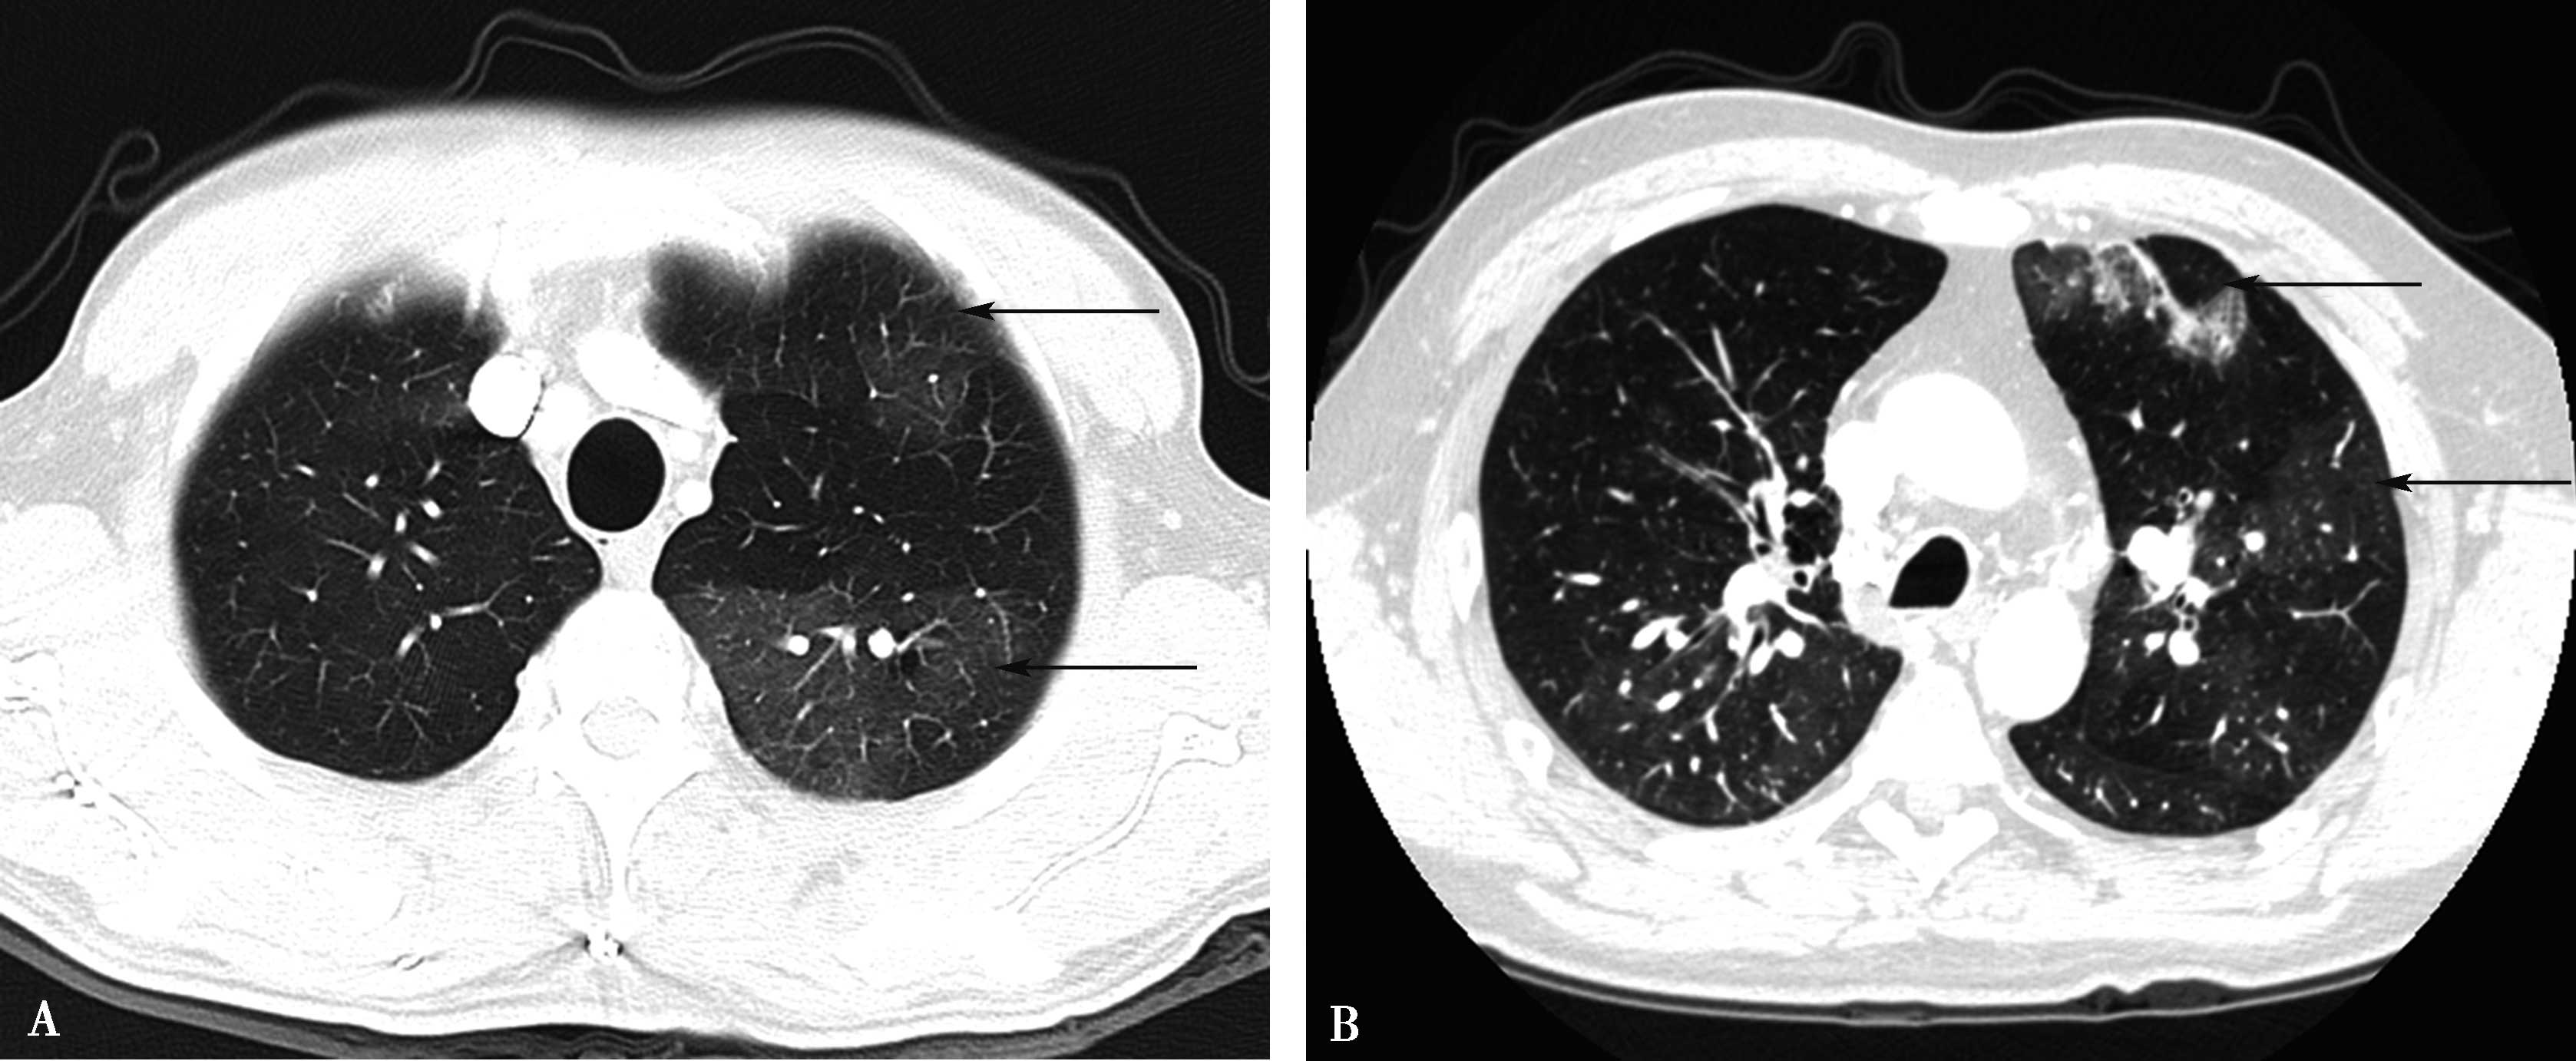

3.支气管扩张

三分之二的CTEPH患者存在有圆柱形支气管扩张(图8-4-27)。多见于段及亚段支气管水平,一般伴行肺动脉严重狭窄或完全阻塞。这些肺实质征象虽为非特异性,但是在临床工作中,这些征象仍然被视为诊断CTEPH的有力证据。

图8-4-27 A.横断图像(肺窗);B.多层重组(MPR),慢性肺栓塞,合并轻度柱状支气管扩张,支气管管壁增厚(↑)